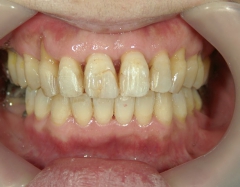

矯正歯科(全顎ワイヤー矯正)治療後

矯正歯科 治療後